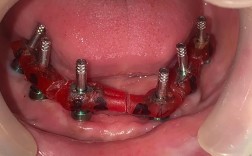

二期手术(暴露种植体):

(图片来源网络,侵删)- 如果种植体完全埋入牙龈下,需要再次小手术切开牙龈,暴露种植体顶部连接平台,安装愈合基台,引导牙龈成型。

- 图片要点: 切口、暴露种植体、安装愈合基台的过程示意图或照片。